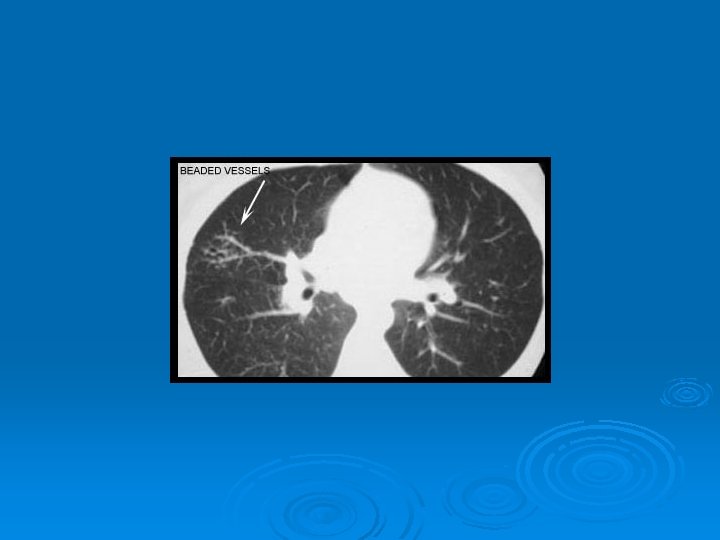

HRCT Ø Akciğer grafisine göre daha duyarlı Ø Paratrakeal, pretrakeal, paraaortik ve subkarinal adenopatilerde tespit edilebilir